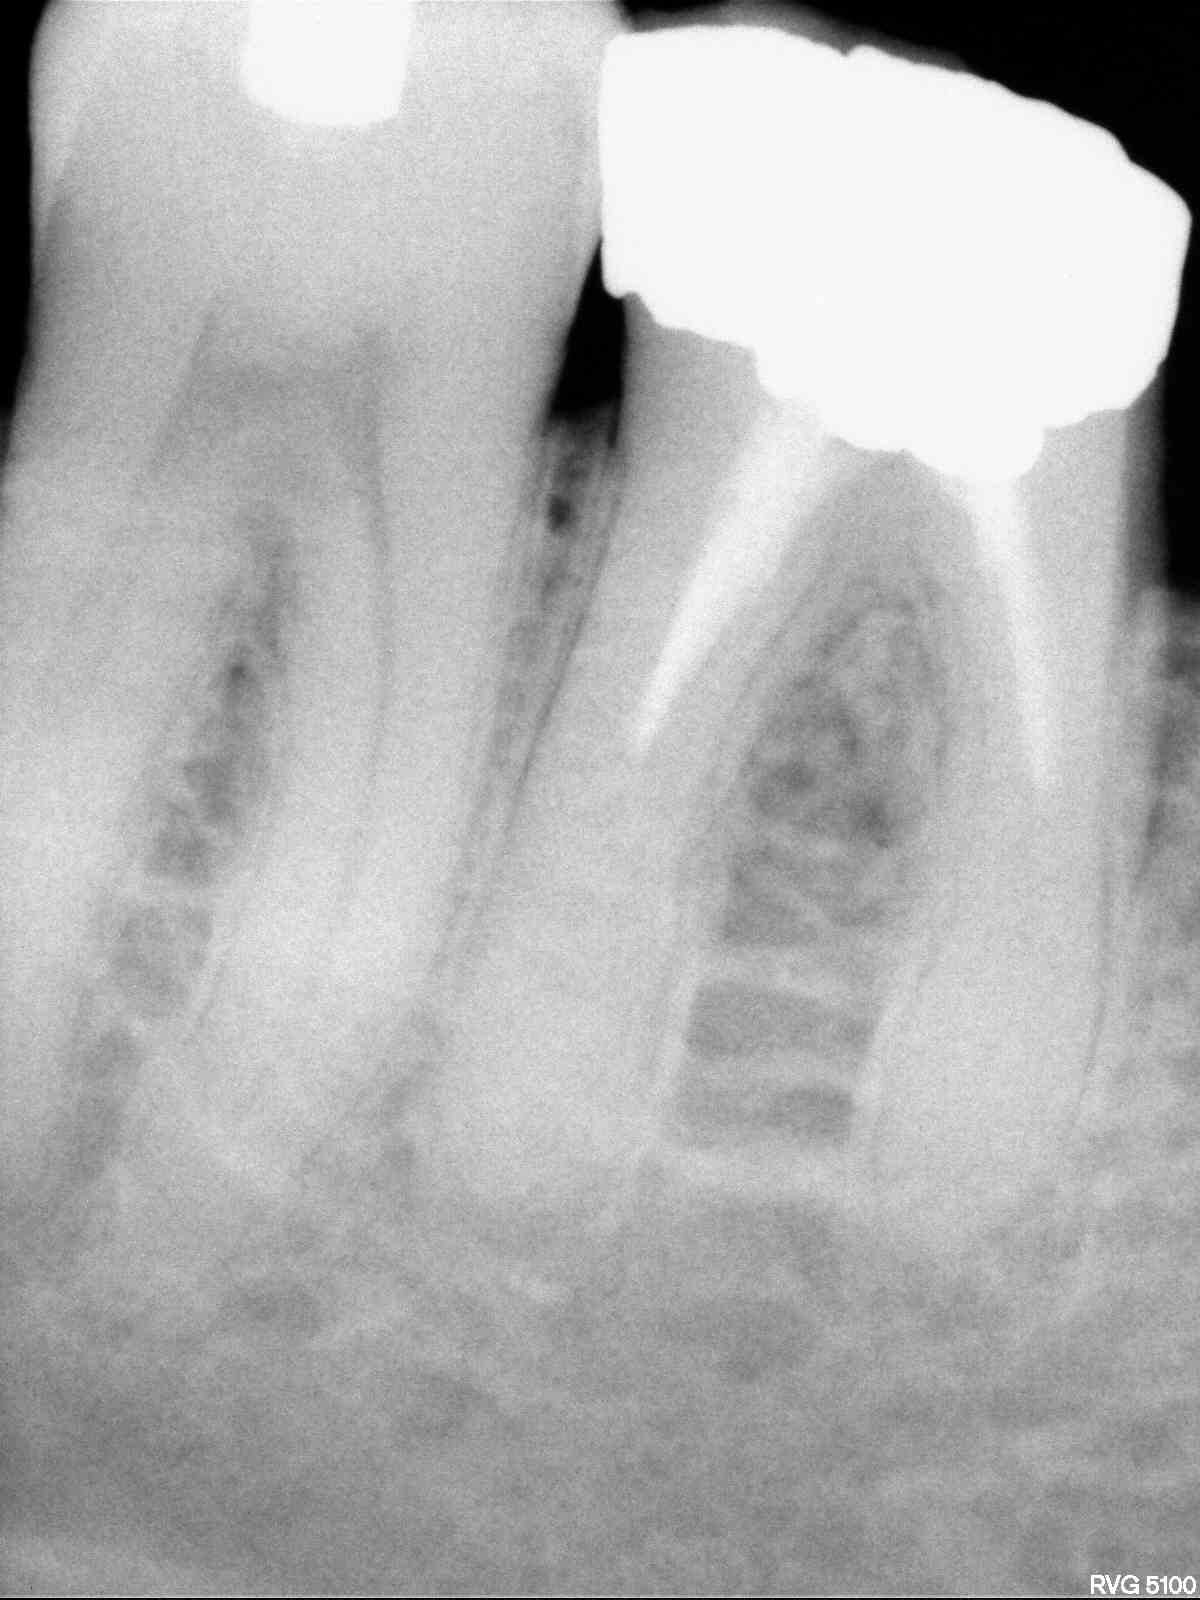

Radios1 dxb8my - Eugenol

Radios2 kprrcu - Eugenol

Radios3 auio0x - Eugenol

Radios4 pfsefa - Eugenol

Radios5 uwurgt - Eugenol

Radios6 ycayfo - Eugenol

Des inlay core... Des endos moisies... C est un français.

Ah ? C'est un français il a des inlay cores et des endos pourries. Ca réduit considérablement les recherches. -))))

maladie dentaire diffuse + antécédent de choc (11 racine fracturée)